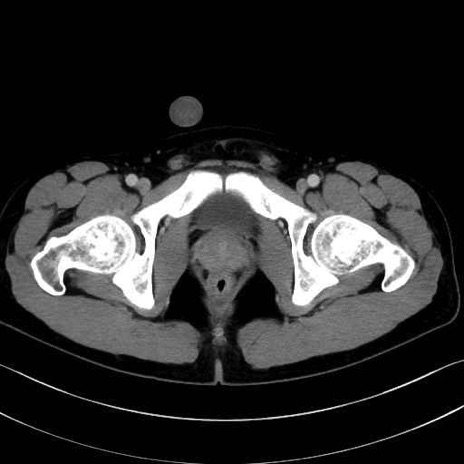

梨状筋(piriformis muscle) のCT画像の解剖

梨状筋 (Piriformis)

内閉鎖筋 (Obturator internus)

外閉鎖筋 (Obturator externus)